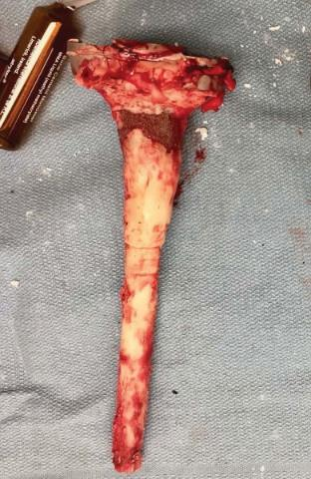

图6  (A)取出胫骨柄锥和布满骨水泥的胫骨延长杆,整块取出。(B)将柄锥和延长杆之间的水泥移除,以创造一个空间来放置尖嘴钳,以便取出假体。